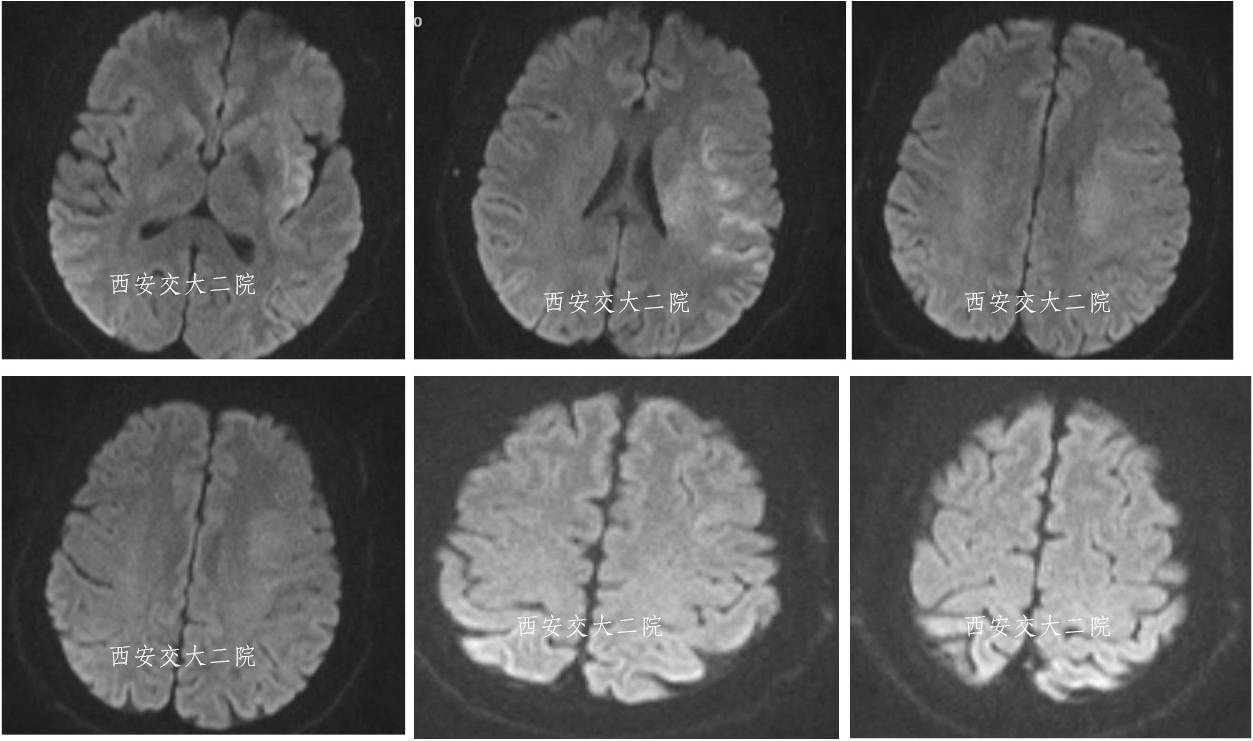

术前DWI

病后2小时动脉推注阿替普酶5mg,无果;solitaire AB(4*20)取栓,闭塞的MCA再通。

术后即刻病情及脑CT

术后24小时脑CT

术后病情变化

术后24h仍呈混合性失语,右侧肢体肌力Ⅴ-级。

术后48h言语恢复正常,右侧鼻唇沟略浅,四肢肌力Ⅴ级,转心外科继续准备手术。